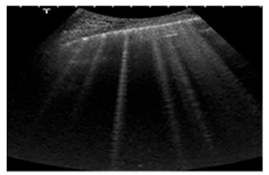

| Acute cardiogenic pulmonary oedema | Number of hyperechoic vertical lines increased, extending from the pleural line and radiating to the edge of the ultrasound field, associated with pleural effusion (without thickening of the pleural line). | ![]() |